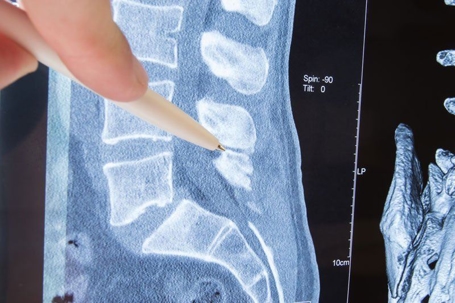

Pen pointing out stenosis on a scan

Imaging tests can include x-rays, a CT scan, or an MRI scan. Each test comes with different benefits. Your doctor will help guide you to the test best suited for your medical and financial needs.

CT scans use x-ray technology combined with an injected dye. The dye is useful because it’s able to illuminate soft tissue damage on an x-ray. This test will help your doctor determine if there is any bone or tissue damage.